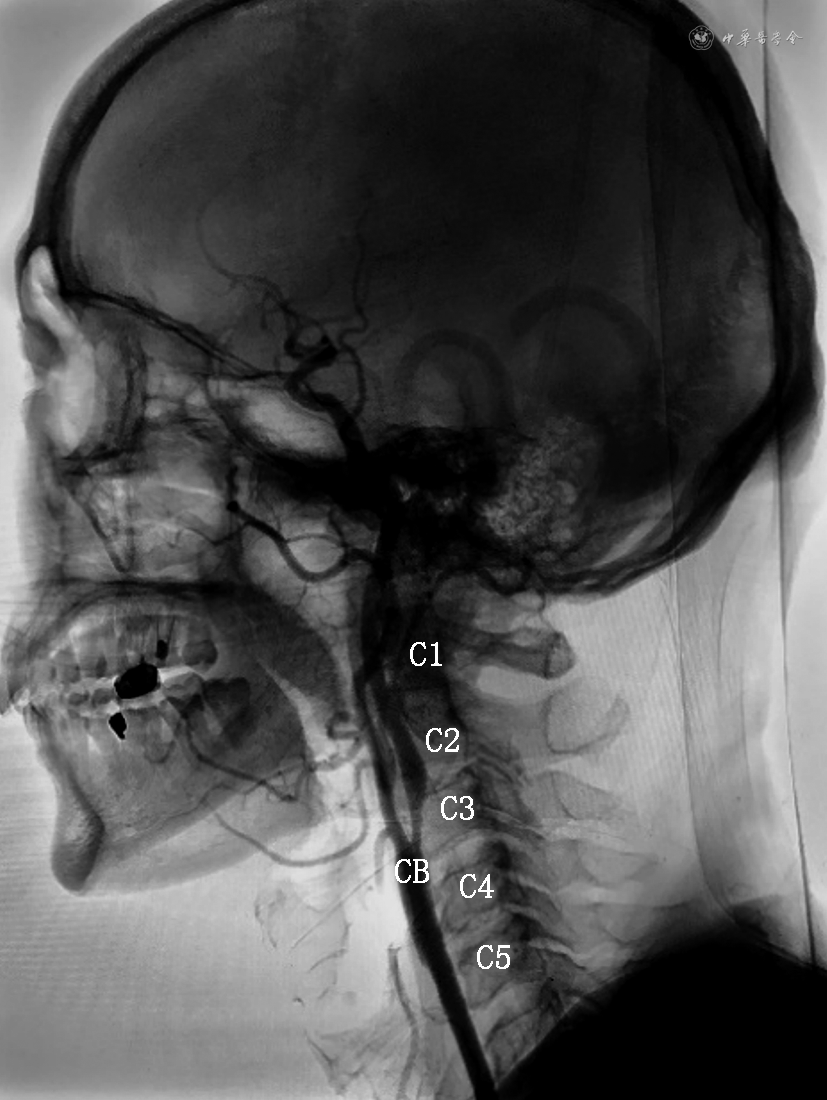

2. 颈动脉DSA相关数据获取方法:在DSA室无菌操作台下进行。局部麻醉后,穿刺股动脉或者桡动脉,先行主动脉弓上血管造影。随后导管分别超选入左、右侧颈动脉,行颈动脉3D造影。影像数据保存在CT工作站,经图像测量获得所需参数。(1)按颈动脉分叉位置对应颈椎水平:分为C2、C2~C3、C3、C3~C4、C4、C4~C5、C5(图1);(2)测量颈长:下颌角到锁骨中点的垂直距离定义为颈长(图2);(3)颈内动脉形态定义与分类:参考Weibel和Fields[3]的颈内动脉颈段走形异常分类标准,即根据扭曲程度分为3类:迂曲:指颈动脉非线性延伸成钝角;扭曲:指颈动脉扭曲成1个或多个锐角;盘曲:指颈动脉以横轴盘绕成1个袢(图3);该分类方法简便易行,能直观反映扭曲的严重程度。本研究根据颈内动脉扭曲程度,将颈内动脉形态分为颈内动脉扭曲组(包括颈内动脉扭曲和盘曲)和颈内动脉非扭曲组(包括颈内动脉正常和迂曲)。

注:CB为颈动脉分叉;C1为第一颈椎;C2为第二颈椎;C3为第三颈椎;C4为第四颈椎;C5为第五颈椎